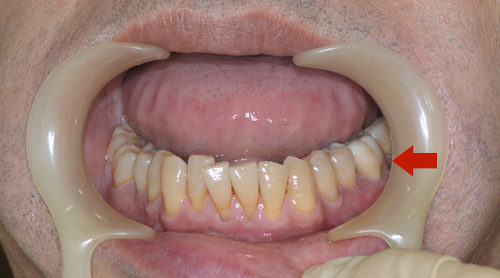

向かって右の前から6本目の歯がオールジルコニアクラウン

オールジルコニアクラウン

オールセラミッククラウンと比べて透明感はありませんが、強度があり、欠けることがありません(歯ぎしりのくせがある人でもご利用いただけます)。また、歯を削る量が少なくすみます。